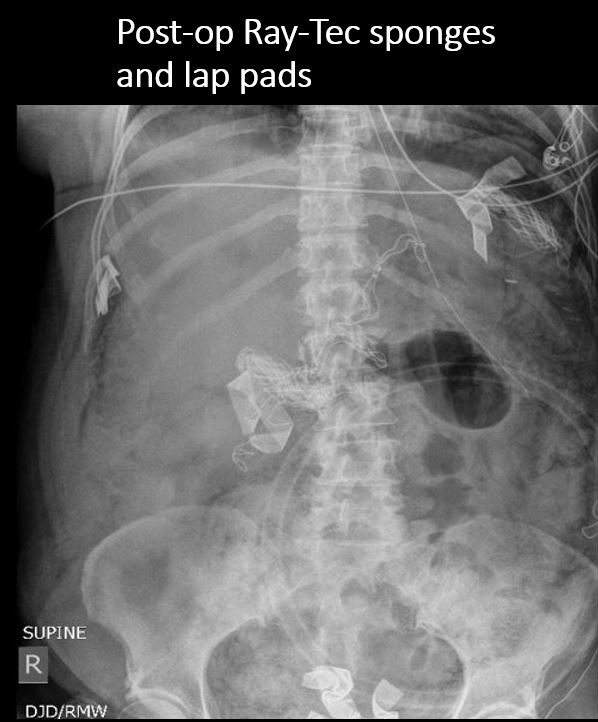

There is an unexpected radiopaque foreign body or incidental non-surgical foreign body in the abdomen or pelvis. [Yes/No]